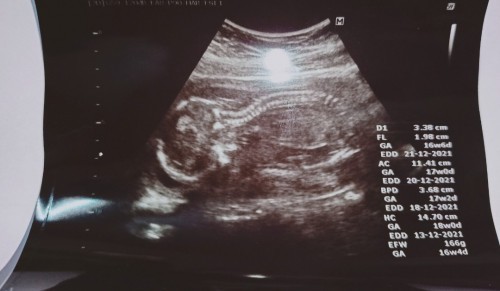

สอบถามเป็นความรู้ค่ะแม่ๆ แม่ท้องได้17+3 ที่ผ่านมาเวลาซาวด์จะตรงมาโดยตลอด แต่รอบนี้คำนวณได้แค่ 16+4

แสดงว่าน้องตัวเล็กรึป่าวคะ หรือ เป็นเรื่องปกติที่พบได้โดยทั่วไปเอ่ย

16+4 ประมาณจาก efw คือน้ำหนักของน้องค่ะ อาจจะต่ำไปนิดนึง